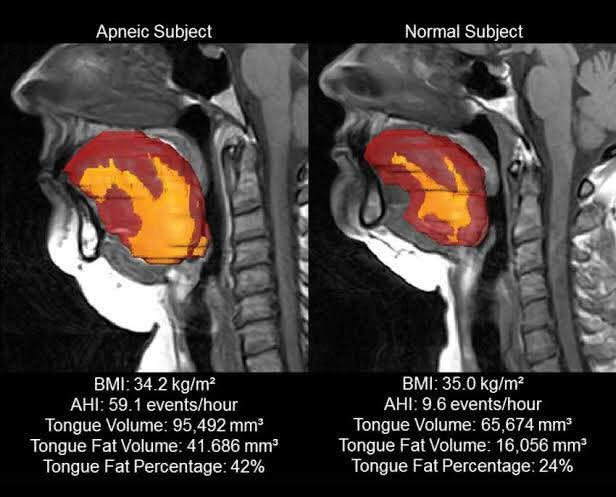

หน้าหลัก > ความรู้ทั่วไป ความรู้ทั่วไป 16 พ.ย. 2568 เลือดจาง” ไม่ใช่แค่ซีด — แต่มันคือภาวะที่ร่างกายขาดออกซิเจนเรื้อรัง 29 ต.ค. 2568 นี่คือสภาพใยประสาทในสมองคุณที่เต็มไปด้วย ‘ขยะพิษ’ (β-amyloid) 31 ส.ค. 2568 "การตรวจที่จำเป็นและเหมาะสม" เป็นสิ่งที่เพียงพอแล้ว 21 ส.ค. 2568 3 สิ่งง่ายๆ ที่ช่วยลดความเสี่ยงมะเร็ง 19 มิ.ย. 2568 📌 สรุปวิธีสร้างฮอร์โมนไทรอยด์ กว่าจะได้ ไม่ได้ง่ายๆ นะเออ 17 มิ.ย. 2568 เมื่อประมาณ 42,000 ปีก่อน มีสิ่งผิดปกติเกิดขึ้นกับ สนามแม่เหล็กโลก 5 มิ.ย. 2568 ⚠️ ขาบวมแดงข้างเดียวแบบนี้ เกิดได้จากหลายโรค อย่าปล่อยไว้ โดยเฉพาะโรคแรก เสียชีวิตได้ 14 พ.ค. 2568 อ้วน คือ 1 ในสาเหตุที่ทำให้นอนกรน 28 เม.ย. 2568 4 วูบ สถานการณ์ต่างๆ เกิดจากกลไกใดบ้าง มาดูกัน 25 เม.ย. 2568 “หมอประชา” ไขข้อสงสัย ร้อนจัดดื่มน้ำเย็นๆ ทำเส้นเลือดสมองแตกจริงไหม? 20 เม.ย. 2568 อย่า …ขู่ให้ลูกหยุดร้องไห้ …. 30 มี.ค. 2568 1